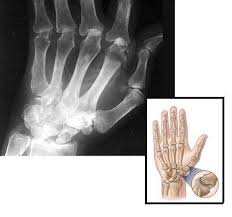

Os termos Osteoartrose, Osteoartrite e Artrose definem uma mesma doença que chega a acometer até 30% da população adulta acima dos 50 anos.

Os termos Osteoartrite e Osteoartrose surgiram posteriormente, para exemplificar melhor a doença Artrose, quando foi descoberto que o osso sub condral (embaixo da cartilagem) participava no processo fisiopatológico da Doença.

Resumindo, quando nos referimos a Osteoartrose, Osteoartrite ou Artroseestaremos sempre falando de uma mesma doença que deve ser tratada o mais precocemente possível, para que a mesma não cause incapacidade.